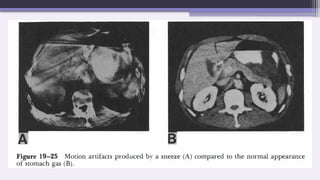

B. Patient Motion

Short scan times have diminished but not

eliminated motion artifacts.

Patient motion can cause misregistration

artifacts, which usually appear as shading

or streaking in the reconstructed image.

Steps can be taken to prevent voluntary

motion, but some involuntary motion may

be unavoidable during body scanning.

Why motion artifacts occur?

The reconstructed image will display an object in motion as a streak

in the direction of motion.

On reconstruction the scanner will average the density of the pixels

covering the motion area.

In some fashion, the intensity of the streak artifact will depend on

the density of the object in motion.

Motion of objects that have densities much different from their

surroundings produces more intense artifacts.

Thus, motion of metallic or gas-containing structures produce

striking artifacts.